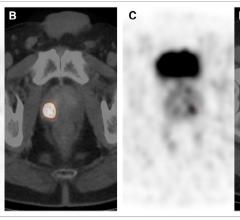

ViewRay Inc. announced new magnetic resonance imaging (MRI) technologies under development for its MRIdian Linac radiotherapy system. Designed to improve tumor and soft tissue visualization, these enhancements to MRIdian's SmartVision MR image guidance are expected to further improve the precision by which radiation is delivered to treat cancer.